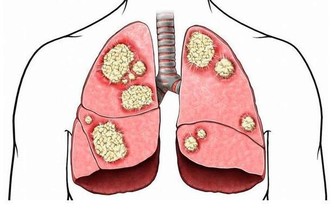

3 、降低腫瘤的發生概率

儘管目前沒有明確的文章提示,肥胖患者患腫瘤的概率一定高,但有研究已經證明,減重後會降低某些激素的分泌,而這些激素,其中有部分就能促進腫瘤的生長。